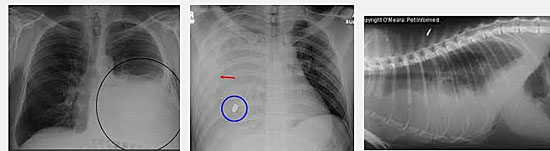

- Chụp x quang phổi: chụp x quang phổi thẳng thường là bước dầu tiên để xác định TDMP. Hình ảnh hay gặp lại là các vùng trắng tại đáy phổi. Nếu TDMP có mặt nhiều thì phim chụp cũng có thể nhìn thấy lượng dịch thay đổi tự do khi bệnh nhân nằm chụp;

- Chụp cắt lớp vi tính (CT scan): Với nhiều lát cắt trên phim chụp sẽ giúp chẩn đoán nhanh và quan sát không những vùng TDMP mà còn khảo sát các phần nhu mô phổi cho các thông tin chi tiết hơn về TDMP và bất thường trong phổi;

- Siêu âm: vừa đánh giá TDMP và giúp hướng dẫn chọc lấy dịch, đồng thời xác định dòng dịch chảy tự do;